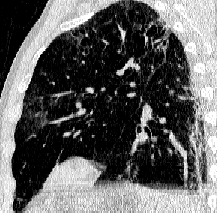

Lung segmentation results for the polymorphic and nonpolymorphic models are shown in Figure 3. Quantitative evaluation of lung segmentations was performed on CT images by comparing the segmentations to ground truth manual segmentations. The Dice coefficient was used to measure volume overlap and the average symmetric surface distance (ASSD) was used to assess boundary accuracy. The ASSD and Dice coefficient results for each of the four evaluation datasets are shown in Table 2. Overall, on the COVID-19 dataset the polymorphic model achieved an average ASSD of mm and average Dice coefficient of . By comparison, the nonpolymorphic model achieved an average ASSD of mm and average Dice coefficient of . ASSD and Dice coefficient results with respect to nonaerated lung volume fraction are displayed in Figure 4. Two-way analysis of variance revealed a significant interaction between model and nonaerated fraction for each evaluation metric, indicating that the regression coefficients with respect to nonaerated fraction were significantly different for polymorphic vs. nonpolymorphic models.

Lobar Segmentation

Lobar segmentation results for the proposed method and PTK are shown in Figure 5 for right lungs and Figure 6 for left lungs. For each image in the COVID-19 dataset (133 images in total), the lobar segmentation result was used to extract the amount of poor aeration () and consolidation () in each lobe. Common phenotypes of COVID-19 affected lungs were identified by hierarchical clustering over the fraction of poorly aerated and consolidated tissue in each lobe. Dendrographic analysis in Figure 7 reveals four primary clusters of patients that were identified by the hierarchical clustering: (a) mild loss of aeration primarily in the two lower lobes without consolidation; (b) moderate loss of aeration focused in the two lower lobes with or without consolidation in lower lobes; (c) severe loss of aeration throughout all lobes with or without consolidation; and (d) severe loss of aeration and consolidation throughout all lobes.